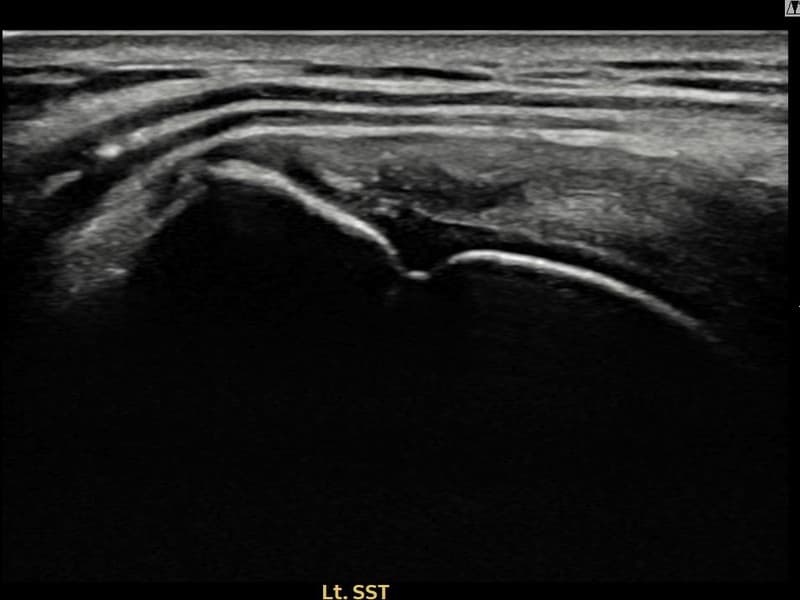

术前

术前超声确认左侧 冈上肌腱 附着部部分撕裂,左侧冈上肌腱回声不连续伴肌腱缺损(11mm × 4mm (肌腱厚度约44%缺损))。术后超声显示撕裂部位充满再生组织,肌腱连续性恢复,回声模式正常化。